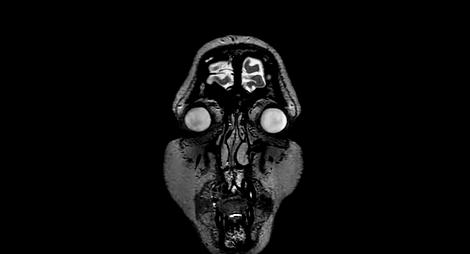

这就要先从核磁共振仪的原理看起:简单来说,我们可以把机器主体那个引人侧目的圆环当做一块强力磁铁。

这些磁铁的存在是为了引起我们人体体内占比很大一部分,且对磁场相当敏感的水分子中的氢原子的反应。

而根据氢原子对磁场的反应,再经过计算机处理,最终就能变成医生所看到的图像。

这就要求开动的核磁共振仪有非常强大的磁力,以至于能够影响我们人类体内分子。